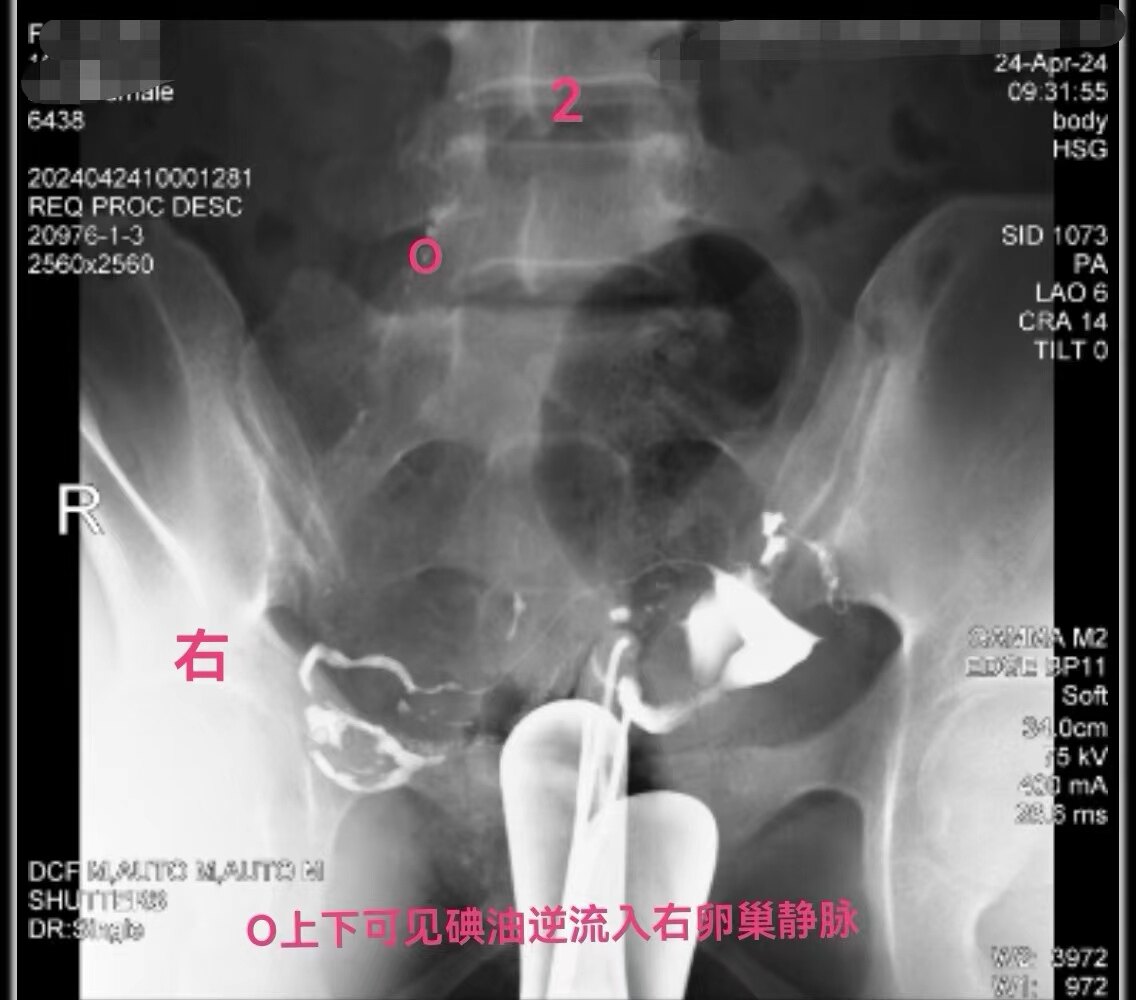

在做子宫输卵管造影检查时:当所用造影剂为碘油,出现静脉和淋巴管逆流时,立即停止造影检查是对的。因为碘油和血液不能相容混合一起,碘油会形成油栓。因此,当碘油进入静脉和淋巴管后会进入下腔静脉,进入右心房,进而进入肺动脉,形成肺栓塞,可危机被检查者生命安全。但是,当所用造影剂为碘水,出现静脉和淋巴管逆流时,可以继续造影检查,直至满足临床诊断后再结束检查。因为碘水和血液可以相容会混合一起,碘水逆流进入静脉和淋巴是安全的。大家好多做过CT增强检查,成年人一般需要用高压注射器要向静脉内快速注入100毫升碘水进行检查,都是安全的。造影注入10毫升左右碘水,即使都进入静脉也没事。这二例,一例碘油造影是一大学附属妇产医院做放射科的,该立即停止造影却没有停止。万幸,逆流进入静脉的碘油少,没有造成严重后果。另外一例碘水造影是一省妇幼保健院放射科做的,不该停止造影检查,反而停止造影检查,未能完成检查,不能给正确诊断。

第一例碘油造影图和报告单